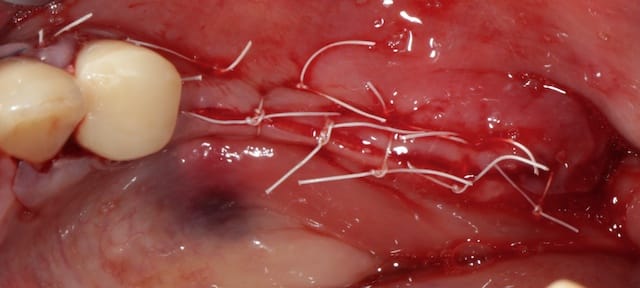

Puisqu'on parlait de ROG verticale, en voici une toute fraiche de ce matin, comblement osseux 50/50 os autogène et Bio-oss le toute recouvert par une membrane PTFE armé titane pinsé.

Plus que 9 mois à attendre ;)

A J+7 ça a l'air de bien se présenter.